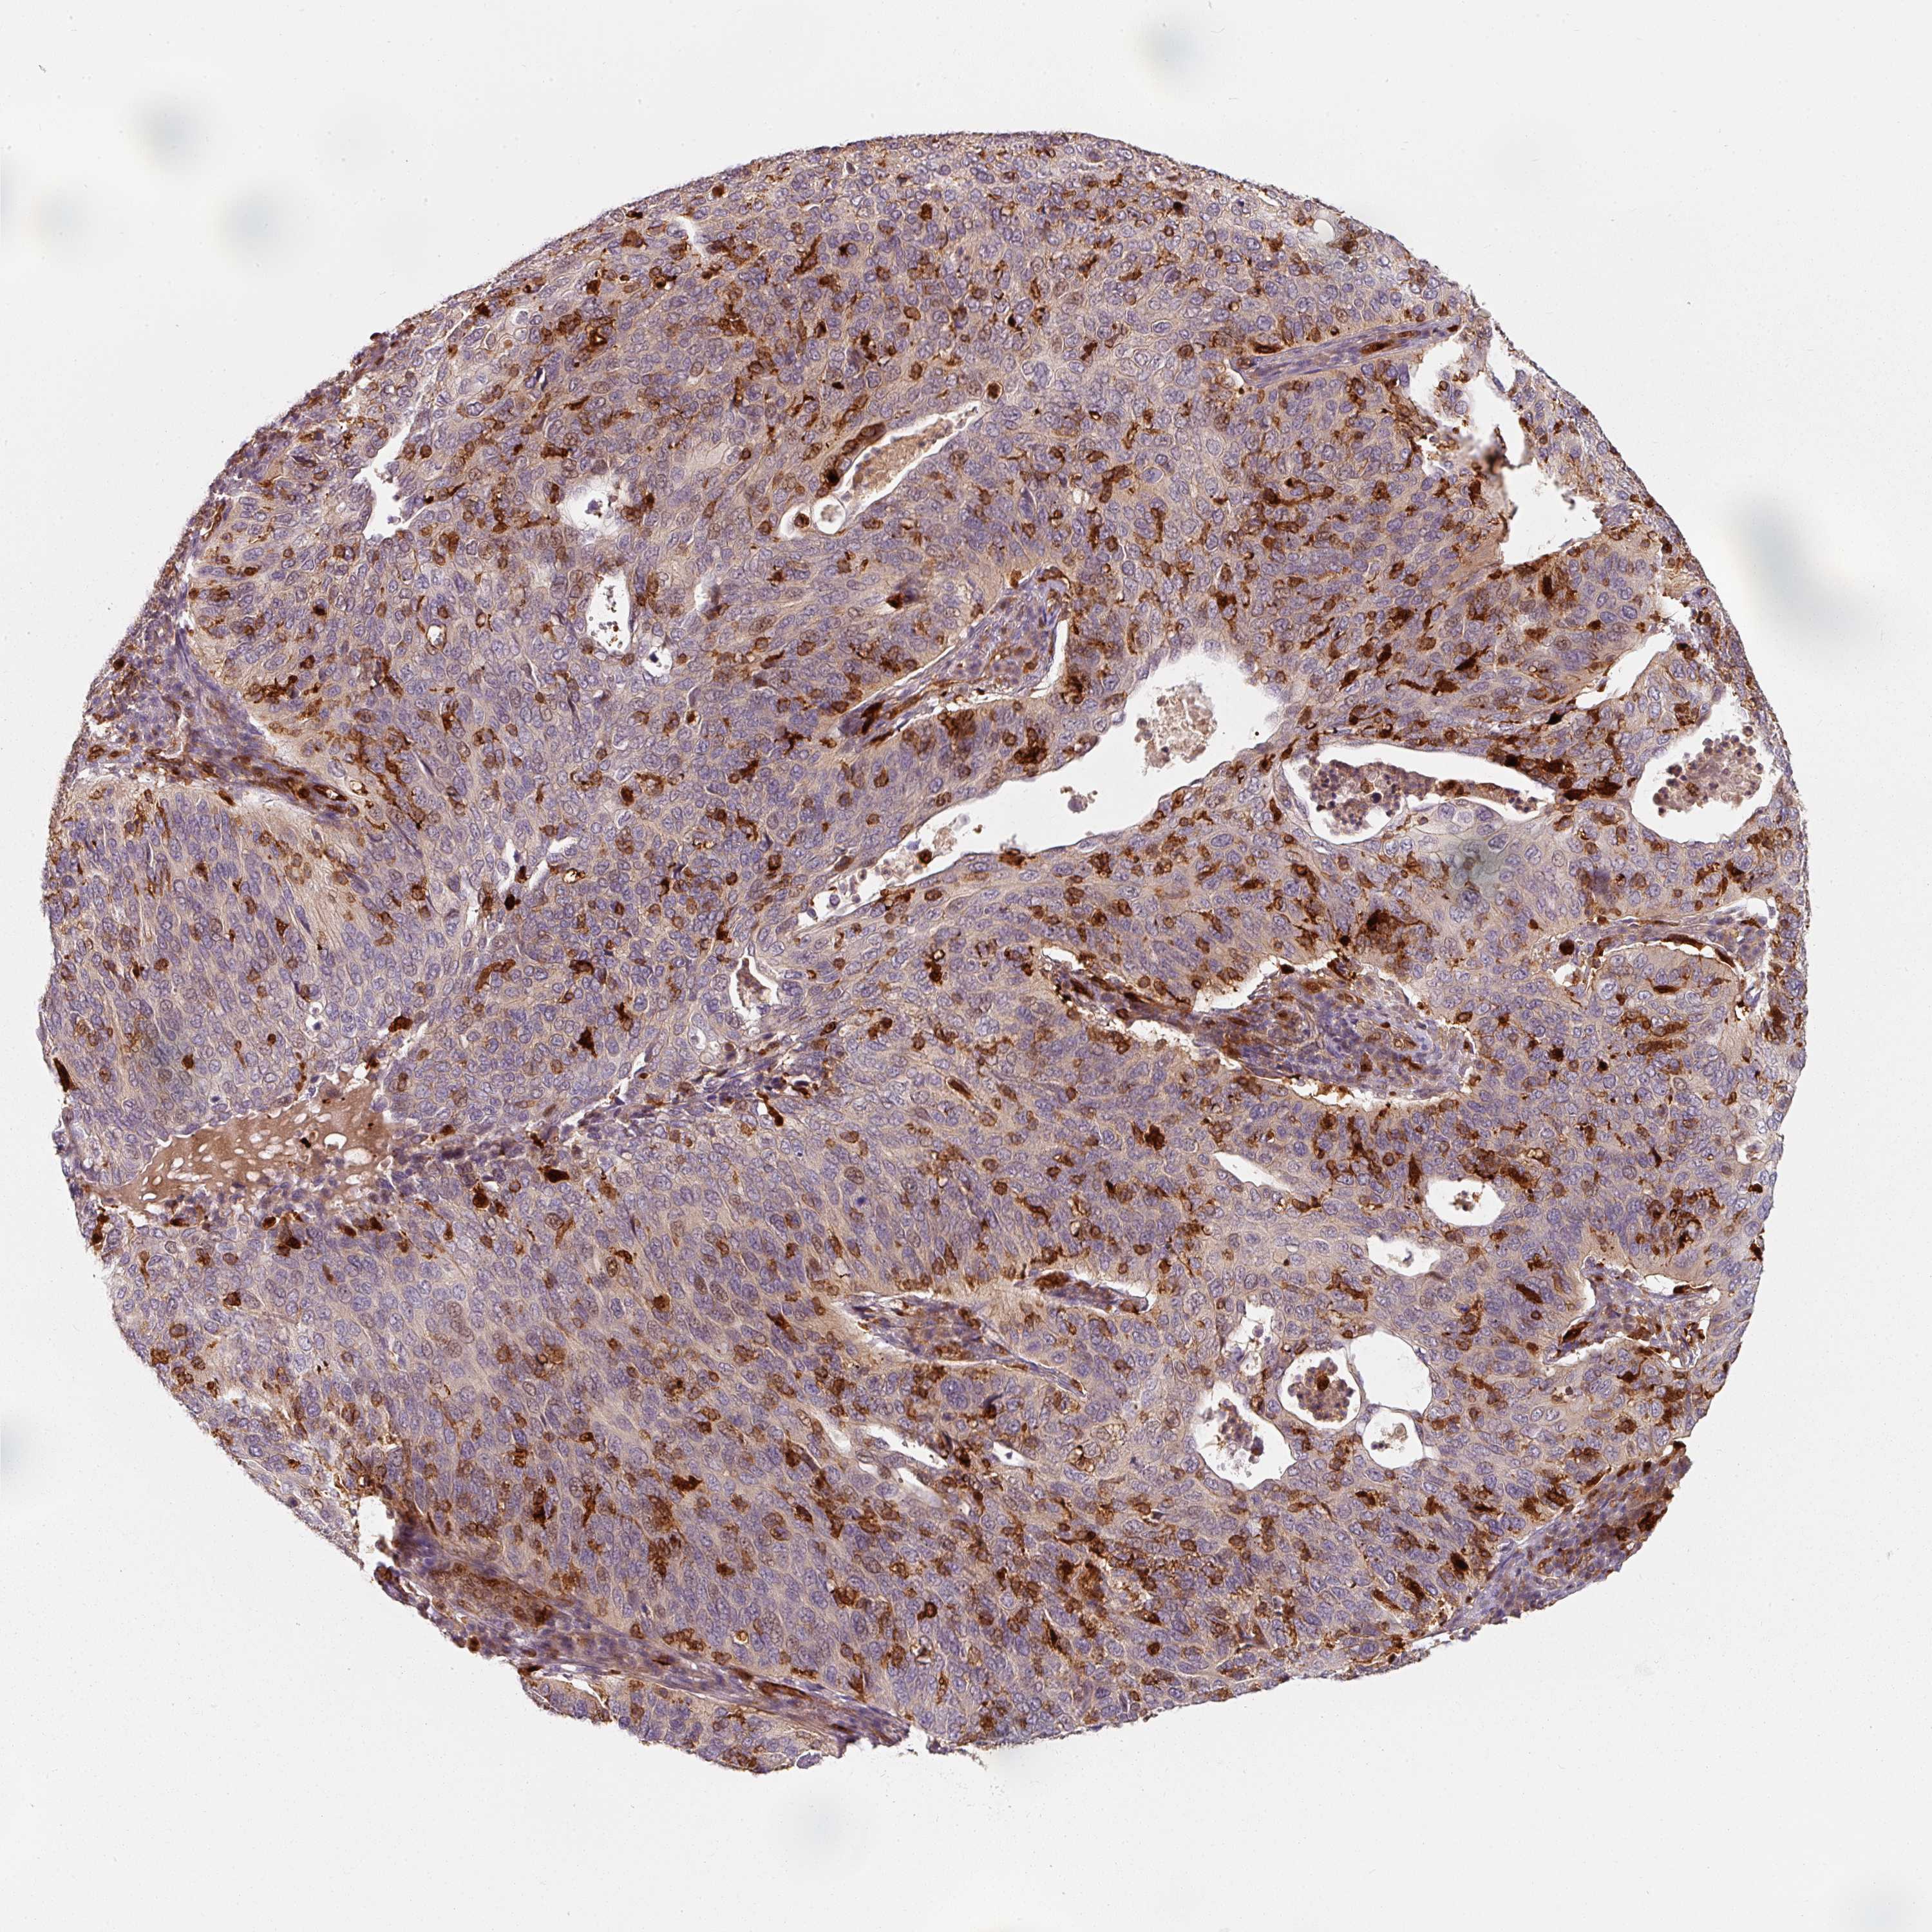

CERVICAL CANCER - Protein expressioni

A mouse-over function shows sample information and annotation data. Click on an image to view it in a full screen mode. Samples can be filtered based on level of antibody staining by selecting one or several of the following categories: high, medium, low and not detected. The assay and annotation is described here.

Note that samples used for immunohistochemistry by the Human Protein Atlas do not correspond to samples in the TCGA dataset.

Antibody stainingi

Antibody staining in the annotated cell types in the current human tissue is reported as not detected, low, medium, or high, based on conventional immunohistochemistry profiling in selected tissues. This score is based on the combination of the staining intensity and fraction of stained cells.

Each image is clickable and will lead to virtual microscopy that enables deeper exploration of all samples and also displays staining intensity scores, fraction scores and subcellular localization as well as patient and tissue information for each sample.

Antibody HPA037403

Antibody HPA037404

Antibody CAB004241

Staining

High

Medium

Low

Not detected

Intensity

Strong

Moderate

Weak

Negative

Quantity

>75%

75%-25%

<25%

None

Location

Nuclear

Cytoplasmic/membranous

Cytoplasmic/membranous,nuclear

Squamous cell carcinoma, NOS

Adenocarcinoma, NOS